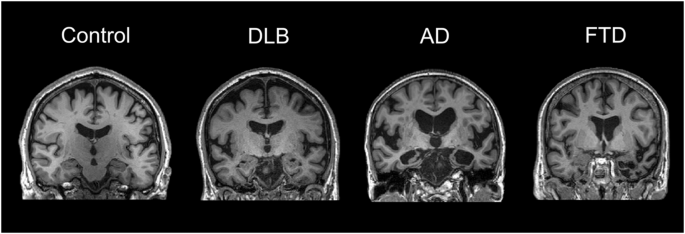

Visualizing the anatomical changes can really help lock these in. Let me see if I can find a good diagram that highlights the different patterns of brain involvement.

MRI is a key diagnostic tool. In Alzheimer's, you'll specifically look for hippocampal atrophy, whereas in Lewy Body Dementia, the atrophy is often more global and less severe early on.